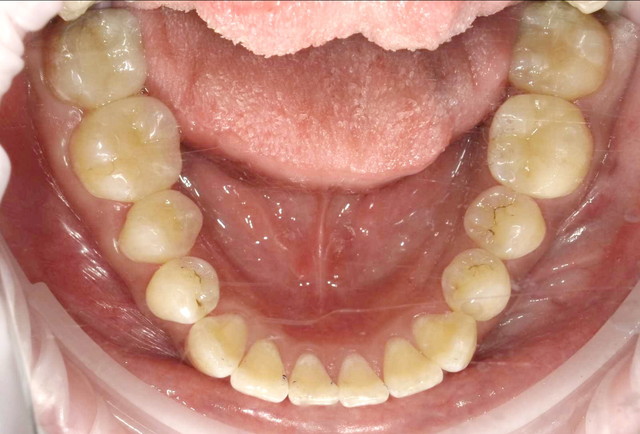

■治療後(下の歯)